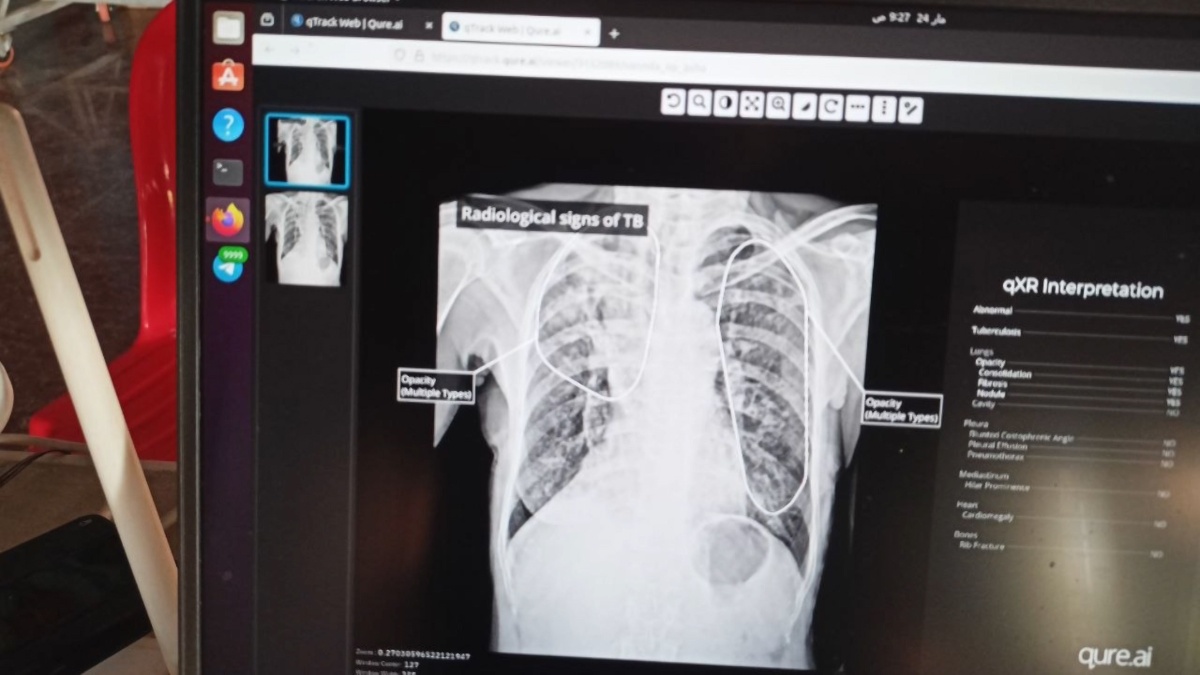

នៅថ្ងៃទី២៤ ខែមីនា នេះ គឺថ្ងៃទិវាពិភពលោកកំចាត់រោគរបេង ហើយតាមរយៈទិវានេះ មណ្ឌលសុខភាពតាមឃុំសង្កាត់ និងអង្គការដៃគូនានា បានបង្ហាញការតាំងចិត្តកាន់តែខ្លាំងក្លារួមគ្នាស្រាវជ្រាវរុករកអ្នកកើតជំងឺគ្រប់ប្រភេទ សំដៅលុបបំបាត់មេរោគរបេងឲ្យអស់ពីក្នុងមូលដ្ឋាន និងសហគមន៍របស់ខ្លួន ខណៈការផ្តល់ថ្នាំ ព្យាបាលជំងឺរបេងនេះ គឺមិនមានគិតថ្លៃសេវាអ្វីទាំងអស់ នៅតាមមណ្ឌលសុខភាពនៅទូទាំងប្រទេស។

បើតាមលោក ប្រាក់ វណ្ណារ៉ា ប្រធានមណ្ឌលសុខភាពស្វាយរលំ និងអង្គការដៃគូ នៅក្រុងតាខ្មៅ ខេត្តកណ្តាល បានថ្លែងប្រាប់BTV នៅថ្ងៃទី២៤ ខែមីនា ឆ្នាំ២០២៦នេះ ថា មណ្ឌលសុខភាពស្វាយរលំ ក៏ដូចមណ្ឌលសុខភាពនានាទូទាំងប្រទេស គឺសុទ្ធតែអនុវត្តនូវគ្រប់សកម្មភាព និងគ្រប់យុទ្ធនាការរបស់ខ្លួនរួមគ្នាកំចាត់រោគរបេងនៅក្នុងមូលដ្ឋាន ក្នុងសហគមន៍របស់ខ្លួន ដោយមានការចុះផ្សព្វផ្សាយ ចុះស្រាវជ្រាវរុករកអ្នកកើតជំងឺរបេង នៅតាមវត្តអារ៉ាម សាលារៀន តាមផ្សារ តាមទីសាធារណៈ និងក្រុមគ្រួសារណាដែលមានសមាជិកគ្រួសារកើតជំងឺរបេង សំដៅមិនទុកឲ្យពលរដ្ឋណាម្នាក់ នៅសំងំខ្លួនមិនព្យាបាលរបេង។